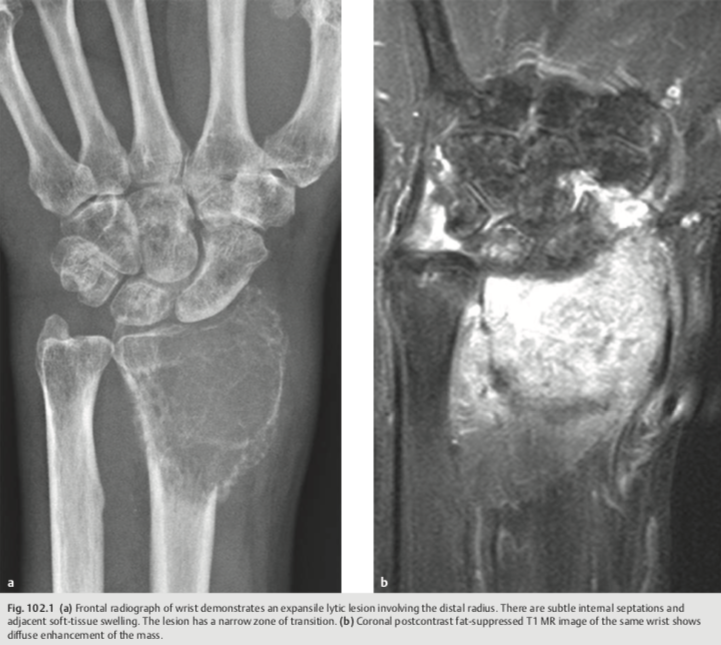

Expansile lytic bone lesion, B9